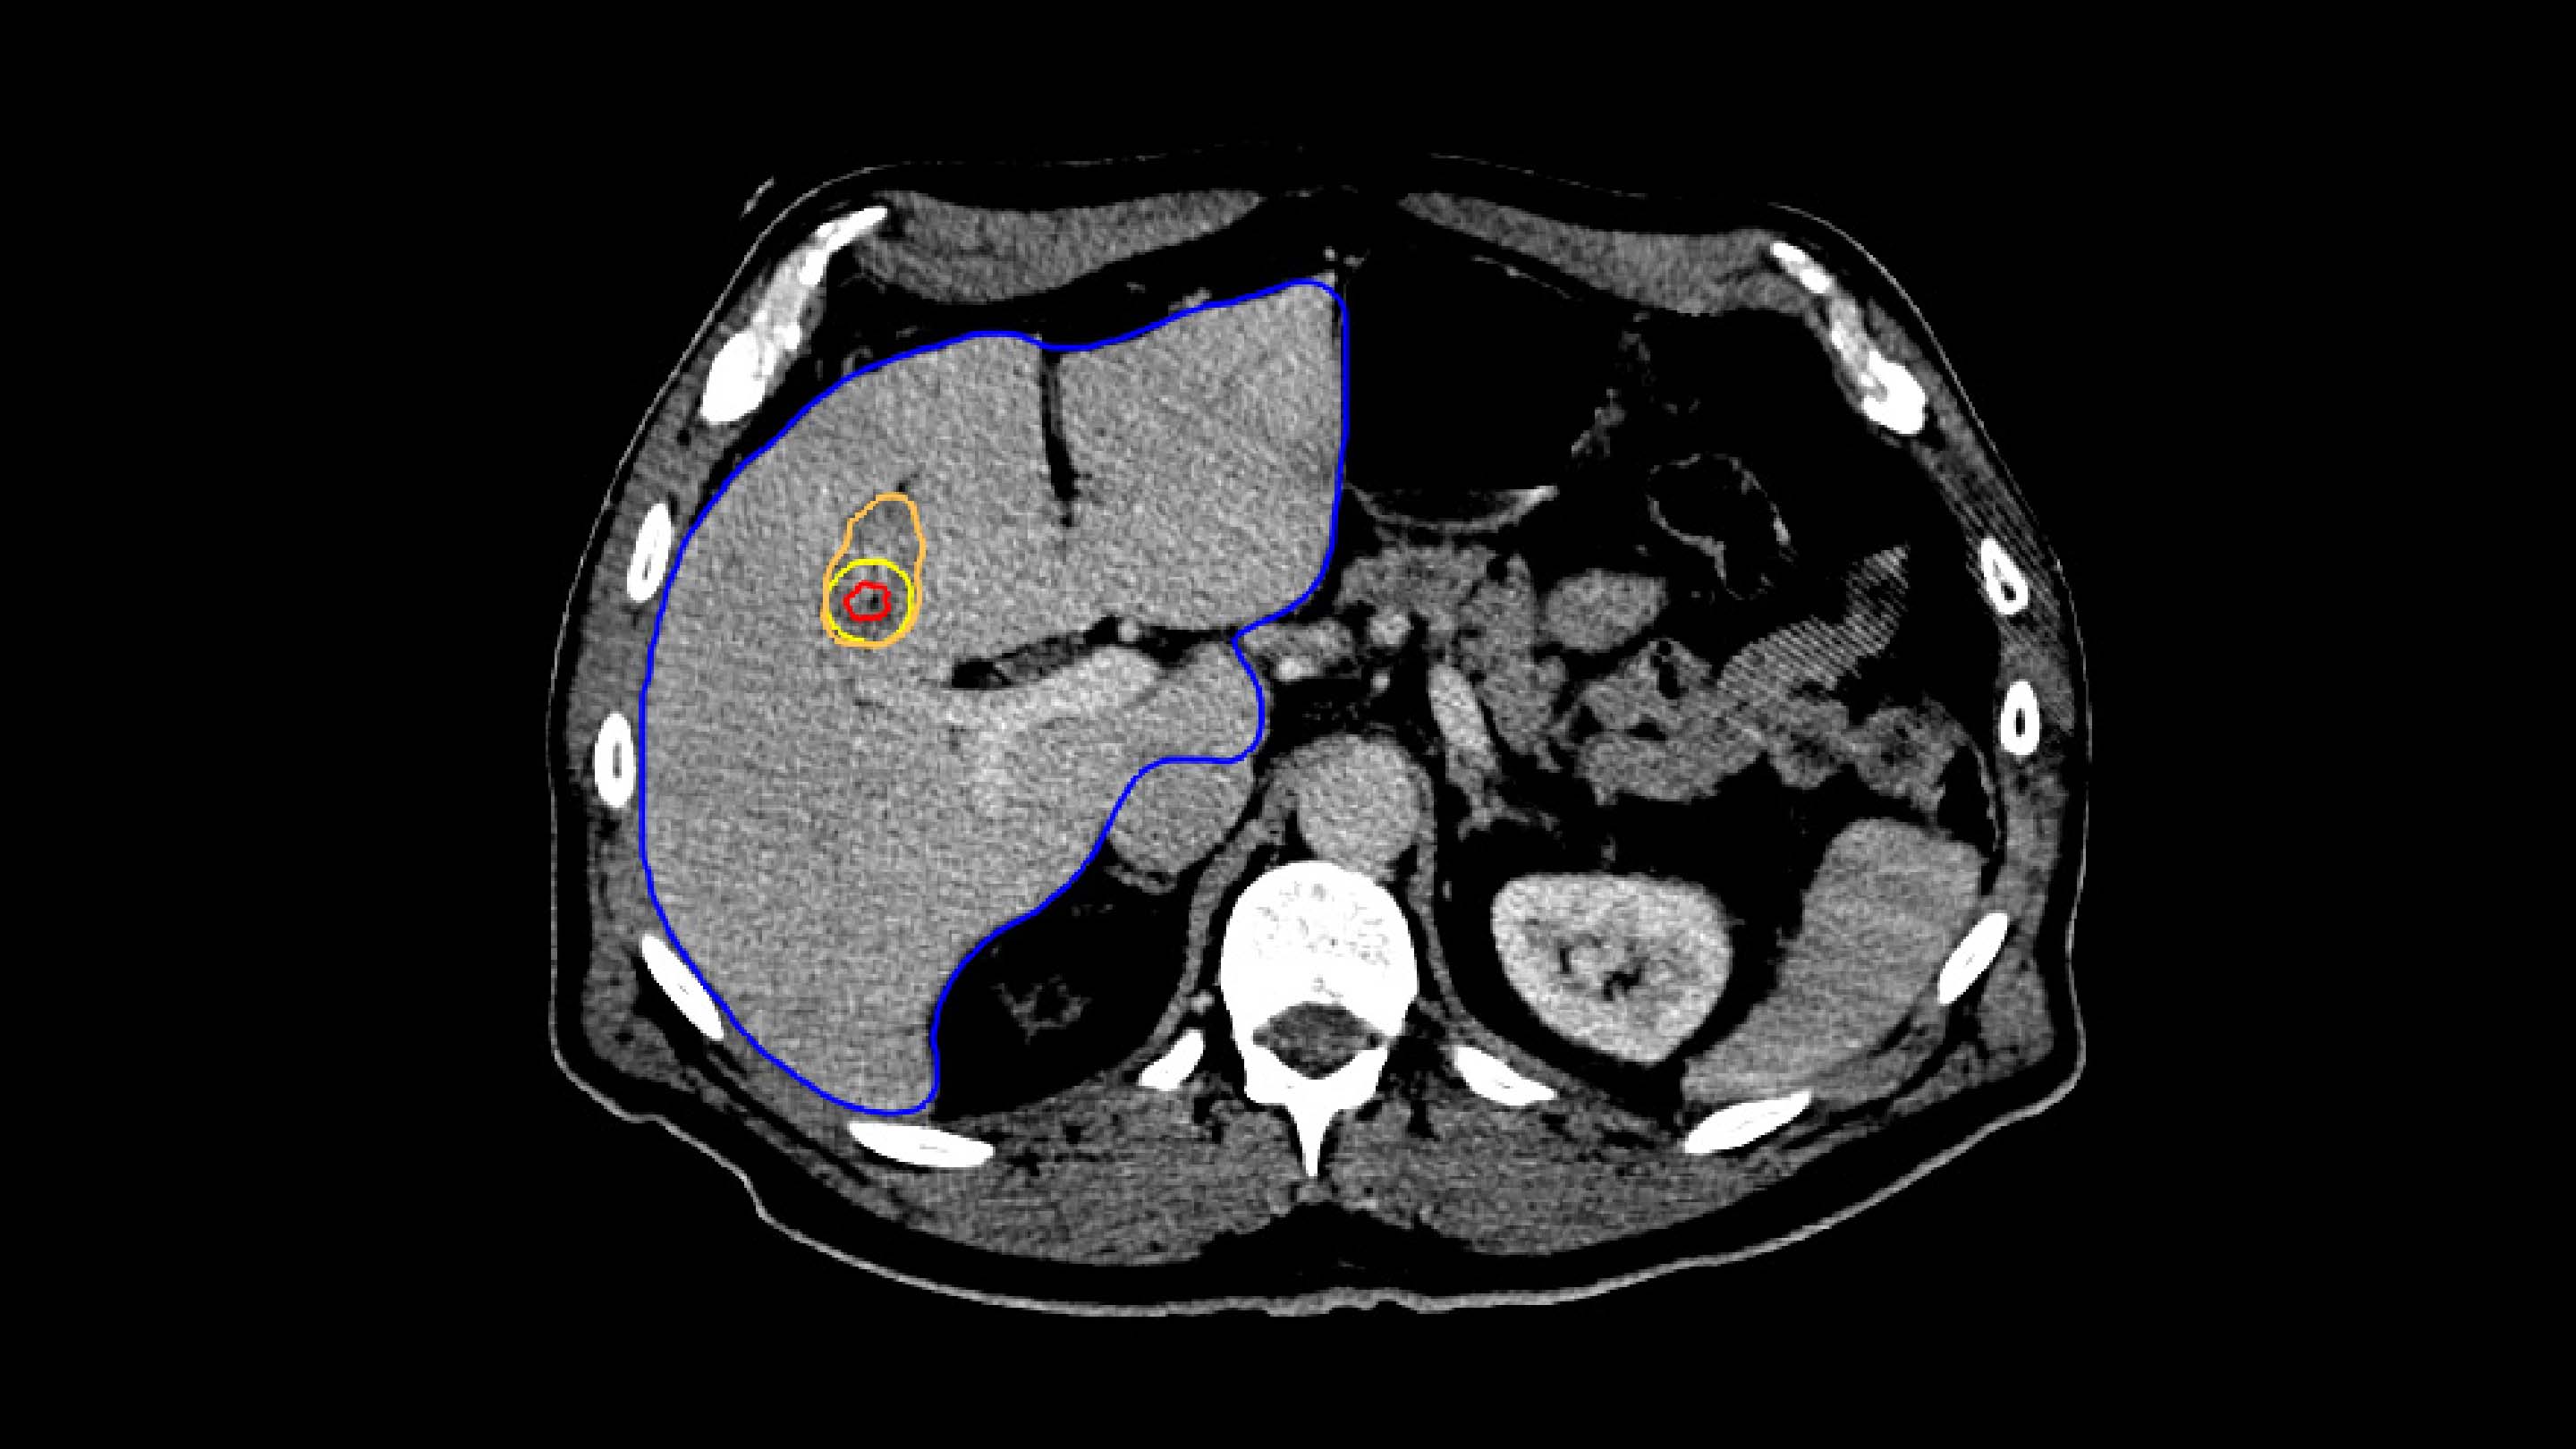

1. PLANNING

The Liver Ablation module offers tools for automatic segmentation of relevant structures. Combined with the ability to place virtual applicators and estimate the ablation zone, our software assists users to determine the optimal number of applicators and their precise placement.